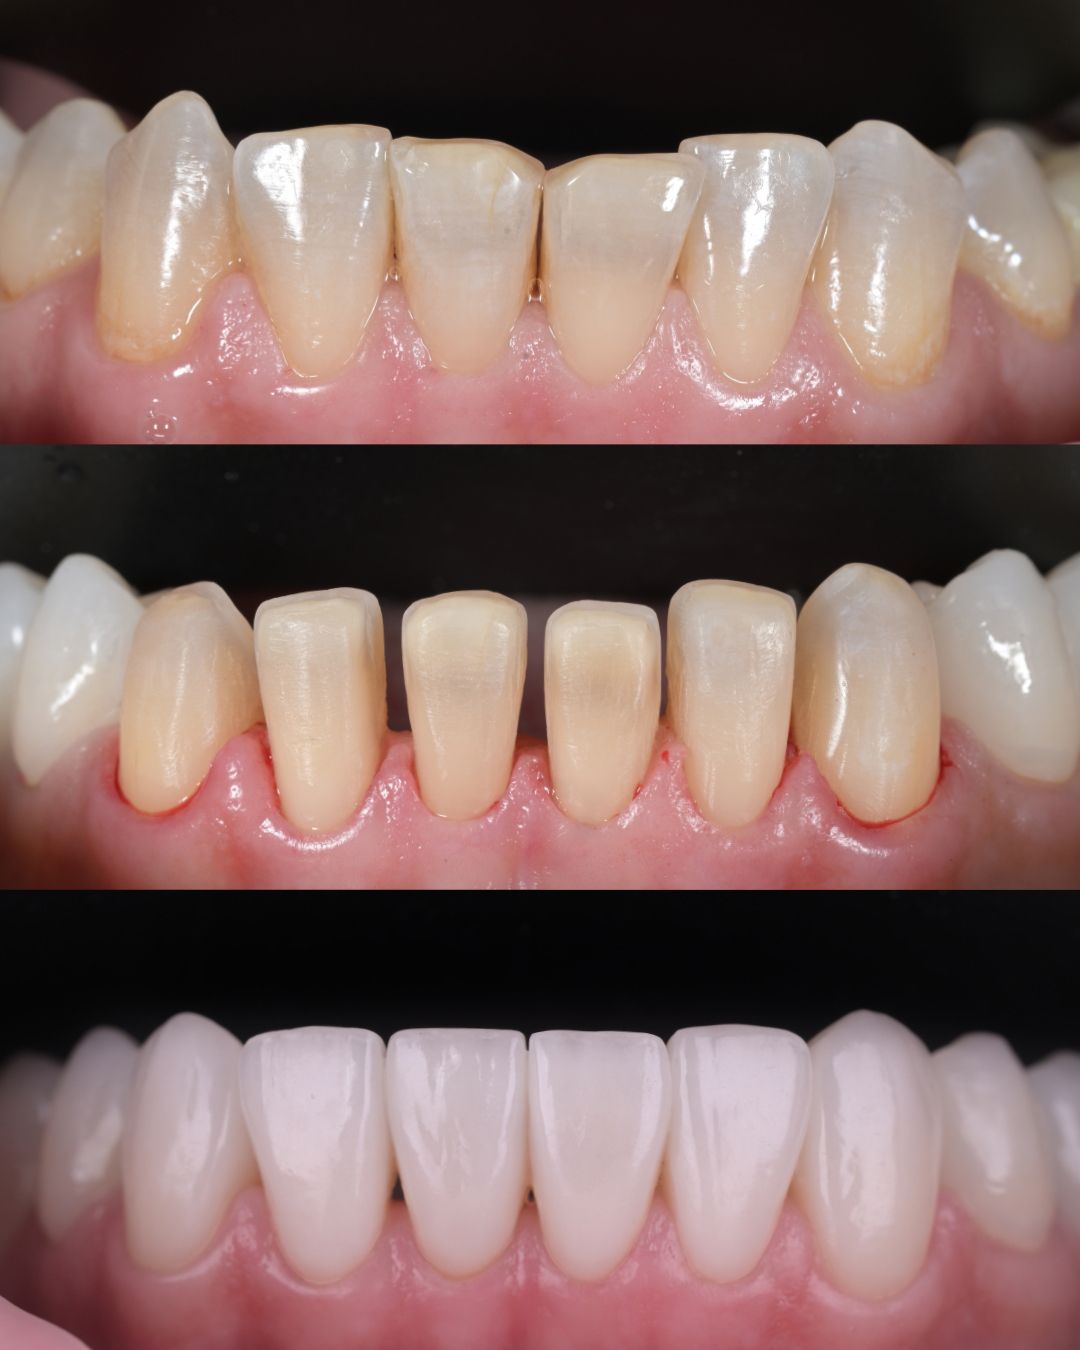

до и после